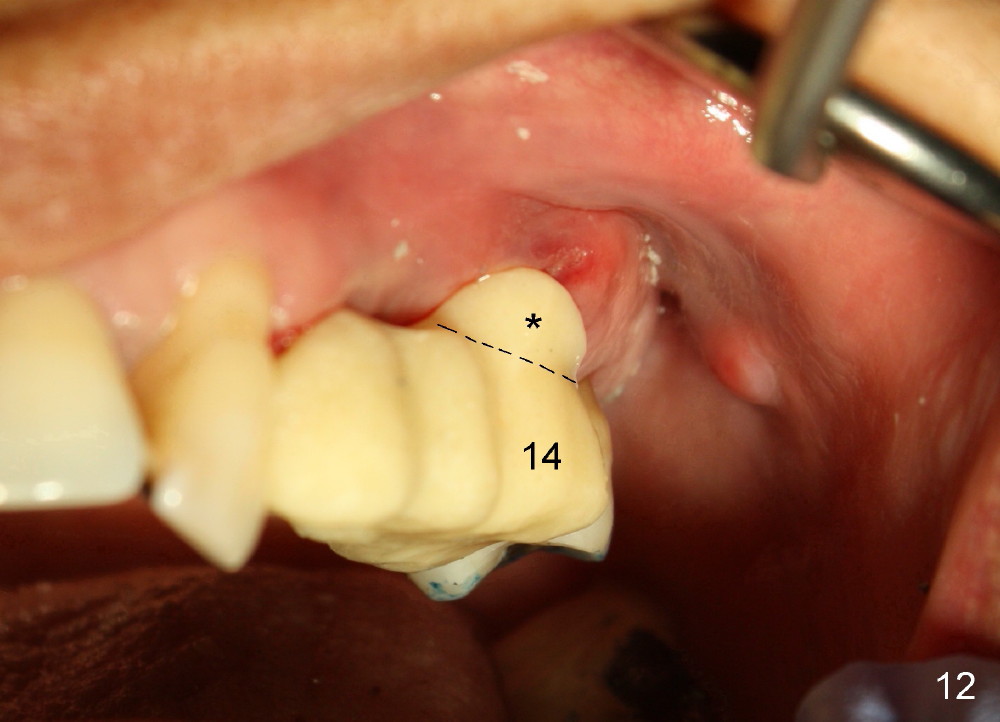

Buccal to #14 implant/abutment is a large defect, which is filled with allograft and Osteogen and covered by collagen membrane (Fig.9 M). The defect at the site of #12 is mesiopalatal, which is repaired in the same fashion (Fig.10: M). The collagen membrane is in turn protected by the "overhang" (extension) of the immediate provisional bridge (Fig.11,12 *). Once the wounds heal (Fig.13, 9 days postop), the extension is trimmed (Fig.14).